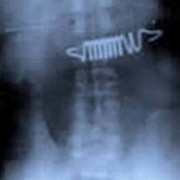

Батерии